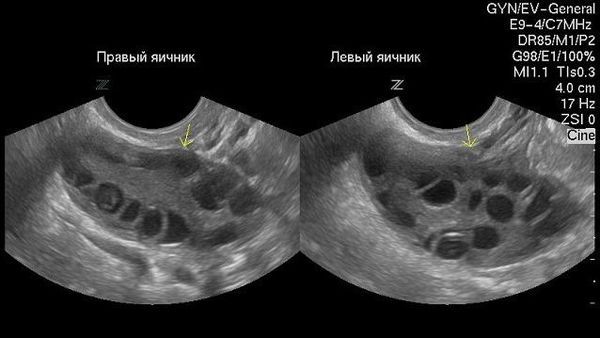

Самым эффективным и простым способом диагностики является УЗИ. Следует сказать, что данное исследование выявляет не только наличие кисты, но и ее размер, строение и содержимое, в результате чего определяется диагноз и методы лечения.

здоровый яичник фото

Такой вид имеют здоровые яичники

киста яичника на узи фото

А такой яичник с кистой